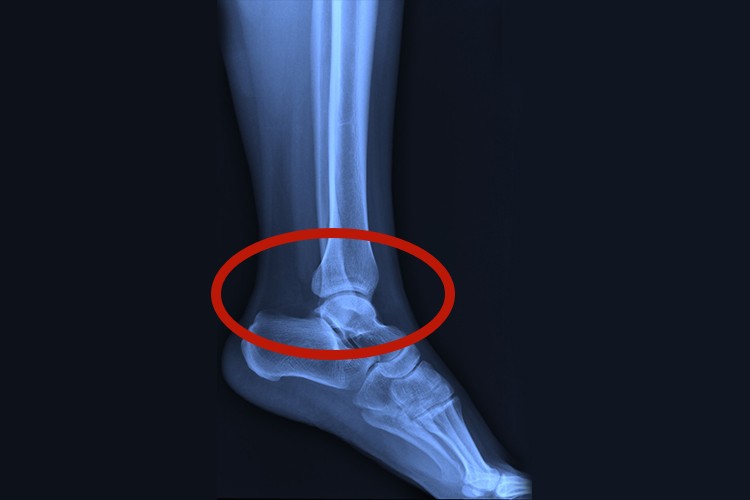

脚踝也称为踝关节,位于足部和小腿相连的位置,由胫、腓骨的下端和距骨的滑车构成,周围有一系列的韧带和软组织加固。

脚踝位于足部和小腿相连的位置,由小腿的胫、腓骨的下端和距骨的滑车构成,胫骨的下关节面及其内踝和后踝与腓骨的外踝共同构成一关节窝,称为踝穴。在关节的周围有一系列的韧带及软组织加固,形成结构独特的踝关节。

由于踝关节的特殊解剖构造,容易发生脚踝部位的损伤,如受到外力后产生韧带拉伤、踝关节脱位、骨折等,可导致明显的脚踝局部疼痛、肿胀,甚至畸形,需要尽快就医诊治。